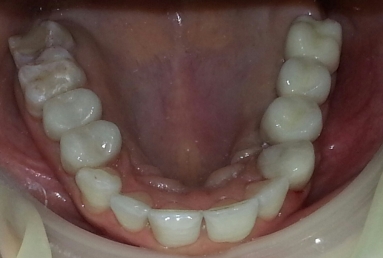

After the osseointegration of the implants three porcelain and zirconium crowns were made. At the same time full ceramic crowns were made for the left canine and the two right premolars, which had deep cavities and needed root canal treatment.

Before starting the prosthetic treatment, the patient wanted a tooth bleaching using the whitening lamp to activate the gel, so the final color for the crowns was chosen according to the color obtained after the whitening.